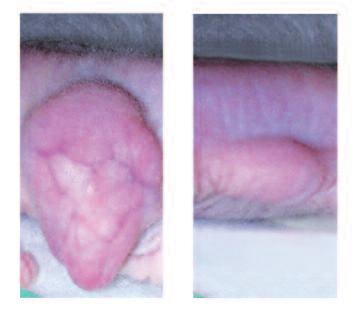

Al termine della gravidanza e in previsione dell'allattamento per il neonato, il segnale ormonale ordina alle cellule del seno di 'avviare' la produzione di enzimi che digeriscono il collagene. Proprio come una ‘squadra di demolizione’ nella vita reale, il loro compito è quello di abbattere l'architettura esistente nel tessuto mammario al fine di consentire la costruzione del tessuto del ‘seno idoneo all’allattamento'. Nella pagina accanto è possibile osservare al microscopio i profondi cambiamenti morfologici (strutturali) che il tessuto mammaria subisce passando dalla fase normale alla fase di allattamento.

Nella figura A è possibile vedere la struttura del tessuto di un seno non predisposto per l’allattamento, caratterizzato dalla struttura densa di tessuto connettivo che circonda il condotto del latte, al centro dell'immagine, in gran parte chiuso.

In netto contrasto, la figura B mostra la struttura cellulare di un seno predisposto all’allattamento, caratterizzato da tessuto connettivo lasso, la presenza di cellule della ghiandola principale necessaria per la produzione di latte (piccoli cerchi bianchi), nonché il condotto del latte ampiamente aperto (al centro dell'immagine).

A. Condotto del latte (chiuso) nel tessuto del seno in condizioni normali

B. Condotto del latte (aperto) durante l’allattamento

A Ripresa di un condotto del latte al microscopio, sito in un seno non predisposto all’allattamento (chiuso)

B. In funzione dell’allattamento si ristruttura il tessuto mammario. Il condotto è aperto e il latte può uscire.